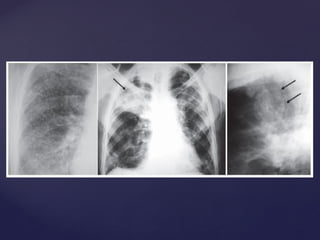

Pneumoconiose  silicose

Doenças causadas

POEIRAS Mineral SiO2 Amorfa ou cristalizada  quartzo, tridimita, cristobalita e trípoli Pneumoconiose  silicose Sílica